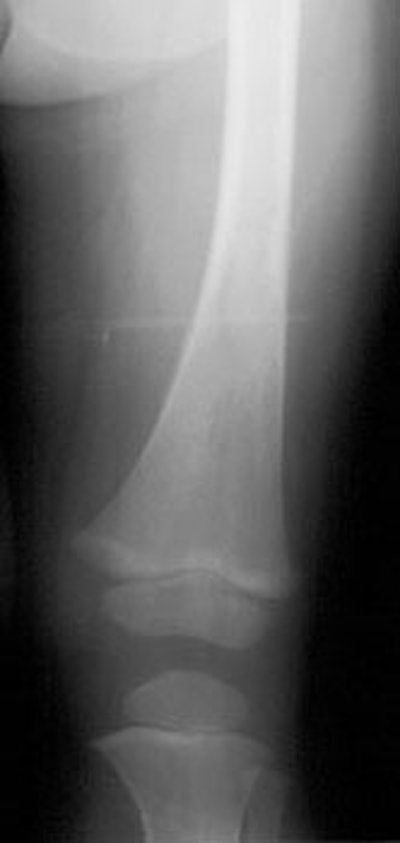

Plain film findings in neuroblastoma include multicentric lytic skeletal lesions, metaphyseal lucent bands, and vertebral body collapse. Calcification is evident in at least 30% of cases [16]. On IVP there is typically inferior renal displacement rather than collecting system distortion (seen in Wilm's)